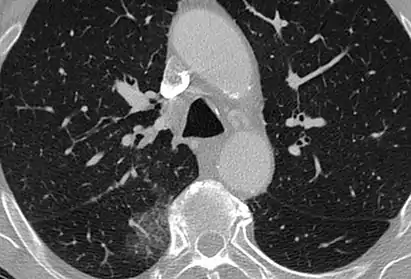

CT image showing centrilobular pattern of GGOs in patient with pulmonary tuberculosis. Note the small, nodular areas of increased attenuation in both lungs.

CT image showing mosaic attenuation pattern in patient with hypersensitivity pneumonitis. Note the alternating, patchy areas of increased and decreased attenuation, particularly in the left lung (screen right).

Centrilobular

Centrilobular GGOs refer to opacities occurring within one or multiple secondary lobules of the lung, which consist of a respiratory bronchiole, small pulmonary artery, and the surrounding tissue.[3] A defining feature of these GGOs is the lack of involvement of the interlobular septum. Potential causes of centrilobular GGOs include pulmonary calcifications from metastatic disease, some types of idiopathic interstitial pneumonias, hypersensitivity pneumonitis, aspiration pneumonitis, cholesterol granulomas, and pulmonary capillary hemangiomastosis.[6]

Mosaic

A mosaic pattern of GGO refers to multiple irregular areas of both increased attenuation and decreased attenuation on CT. It is often the result of occlusion of small pulmonary arteries or obstruction of small airways leading to air trapping.[6] Sarcoidosis is an additional cause of a mosaic GGOs due to the formation of granulomas in interstitial areas. This may coexist with granulomatosis with polyangiitis, leading to diffuse areas of increased attenuation with ground-glass appearance.[6]